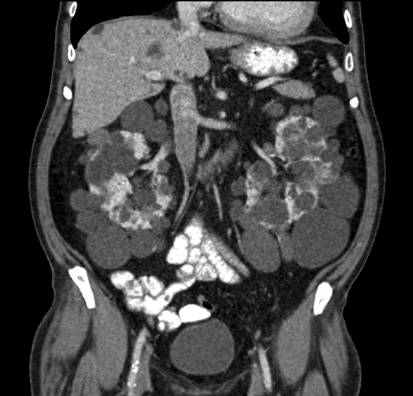

此后,CT的相关技术发展迅速,探测器的个数已能达到数千个,扫描方式也从平移、旋转到多层螺旋式扫描。随着计算机功能、图片处理等技术的提高,现代CT实现了即时获得重建图像及合成三维重建图像,具有抗干扰强、层面连续、图像质量高等优势,广泛地用于检查和诊断。因CT图像属于结构显像,解剖定位清晰,医生能详细观察人体某部位的形态学特点(包括解剖结构、形态、大小、密度),可根据病灶的具体特征进行精确的诊断。

人体腹部的CT图像(图片来自网络)